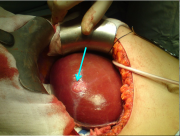

| 15:20, 4 בנובמבר 2012 | אדרנל1114.png (קובץ) |  |

79 קילו־בייטים | Motyk | 1 | |